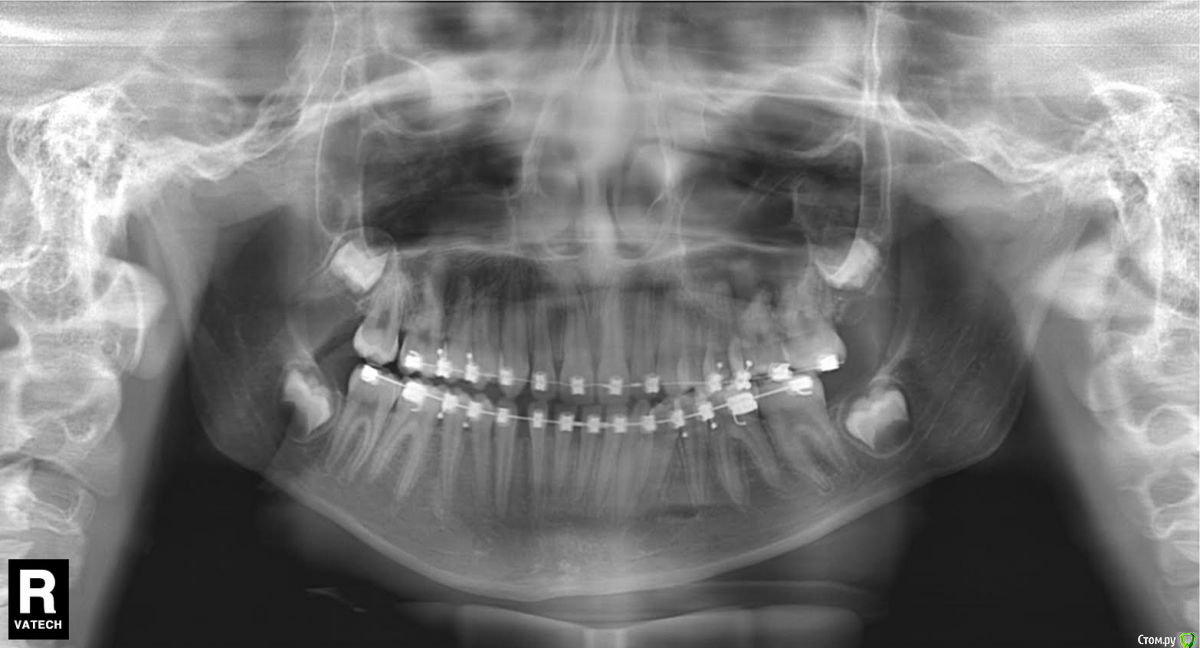

Мама пациента Опубликовано 20 мая, 2016 Поделиться Опубликовано 20 мая, 2016 Письмо на форум стоматологов. Здравствуйте, уважаемые доктора. Извините за много букв, но короче не расскажешь. Дочери 12 лет. Никогда не замечала перекрёстного прикуса, вдруг в июне 2015 г. на регулярном осмотре терапевт сказала, что прикус перекрестный, нужно срочно бежать к ортодонту, а то ребенок «съест» зубы, хотя раньше не говорили об этом. Видимо поспешили с выбором врача. Доктор хорошая, старательная, молодая, но видимо у нас не совсем линейная ситуация, с которой раньше она не сталкивалась. Здоровье, к сожалению, у ребенка не богатырское, парез лицевого нерва был с рождения, дисплазия соединительной ткани – исследованиями не подтвержденная (много гибкости, мало силы и упругости мышц). Поставили брекеты на верхние зубы в июле 2015- 11 лет. Нижнюю челюсть наклеили в ноябре. ОПГ снимок до того прилагается. Кроме него исследований не делали, теперь поняла, что надо было. Все поездки к врачу заканчиваются 3-х-5-ти дневными страданиями. В марте после поездки (наклеили клыки, прорезающиеся нижние 7-ки и поменяли дуги), на следующий день поднялась тем-ра 37,7 и потом 3 недели!!! она была субфебрильная. Анализы крови и м. были нормальные (немного снижены сегментоядерные и повышены лимфоциты). Это сопровождалось головокружением. Лечили синусит. По ВСД по назначению невропатолога сделали исследования (ЭЭГ, УЗДГ- ТГ)- повышено внутричерепное давление (результаты есть). Сделали 4 сеанса у мануального тер., который по его словам «снял блок с шеи…и сделал спину (убрал начинающийся сколиоз)». Головокружения прекратились. Сходили на консультации к хорошим ортодонтам в Москве, к сожалению, никто пока помочь не берется. После одной из консультаций (врач достаточно активно двигала челюсть) опять кружилась голова в течении пары часов. На консультации к челюсно-лицевым хирургам пока не попали, т.к. в Москве к гуру целая история попасть, а конец учебного года и два пропущеннных месяца в школе. Но операцию делать я ей не буду, т.к. риски для здоровья от операции гораздо выше. Будет взрослая сама решит. Случай не простой, время упущено, челюсть выросла криво, но рост еще идет (доктор сказал по ренгену ладони). Неужели в стране нет специалиста, который в комплексе занимается ортодонтией с содружестве в неврологами и мануальными (краниальными) терапевтами. Может кто-то занимается миотерапией (лечебная физкультура для челюстей). Сейчас просто боимся идти к ортодонту менять дуги и доклеивать отвалившиеся брекеты и я, и ребенок. Потому, что 4 недели мучений и по учебе уже пропустили пол-четверти. Ей хочется все бросить, оторвать все брекеты и забыть, как страшный сон. Хотя я прекрасно понимаю, что таким прикус оставлять нельзя, надо попытаться что-то сделать. Что бы вы делали для своего ребенка в этой ситуации? Ссылка на комментарий

Yana guapa Опубликовано 20 мая, 2016 Поделиться Опубликовано 20 мая, 2016 при перекрестном прикусе я бы не ставила брекеты на нижнюю челюсть. Потому что дуга дает расширение (а у вас итак нижняя челюсть больше верхней) если и ставлю брекеты на нижнюю челюсть, то на верхнюю челюсть изнутри (с небной стороны) ставятся кнопки, и пациент носит косые эластики (плюс все зубы должны быть разобщены на накусочных площадках, иначе они никогда не смогут "перепрыгнуть" через бугорки нижних) у вас такого разобщения не вижу, верхние зубы упираются в нижние. здесь хоть кучу дуг поменяй, но все будет стоять на месте. ортодонты, занимающиеся в содружестве с мануальными терапевтами, неврологами И так далее - на каждом углу. только вот результаты..... причина ваших головокружений так и не выяснена? когда нибудь были такие головокружения до постановки брекетов? Ссылка на комментарий

Мама пациента Опубликовано 20 мая, 2016 Автор Поделиться Опубликовано 20 мая, 2016 (изменено) У нее и сильно стало лицо перекошено осенью, когда нижние наклеили. Люди стали видеть, что она кривит лицо, хотя до этого никому в глаза не бросалось сильно. Изменено 20 мая, 2016 пользователем Мама пациента Ссылка на комментарий